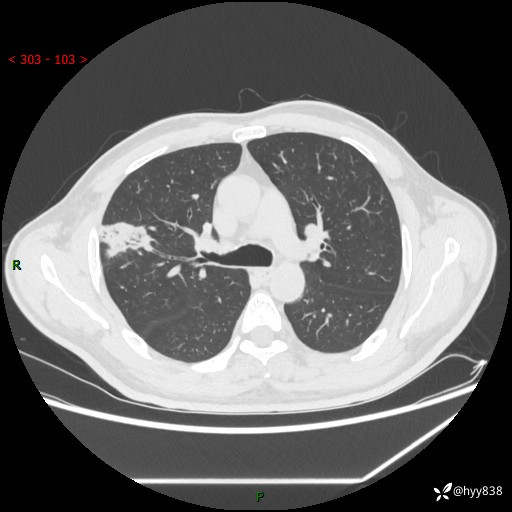

现病史:患者2天前体检完善胸部CT提示:右上肺团块影,炎症可能,肿瘤性病变不除外,冠状动脉钙化,无咳嗽、咳痰,无寒战发热,无恶心、呕吐等其他特殊不适,未予以特殊治疗,现为明确病变性质来我院就诊,门诊以“肺肿物性质待查”收入我科。 起病以来,患者精神、饮食、睡眠可,大小便正常,体力体重较前无明显变化。

胸部CT平扫+增强